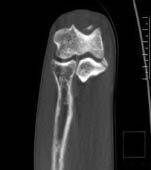

Radiography and computed tomography were performed (Figures 1–3). An aseptic necrosis was detected in the region of the tubercle of the coronary process in the fragmentation stage.

Fig. 2. Computed tomography of the left ulnar process and fragmentation stage of the region of the coronoid process tubercle